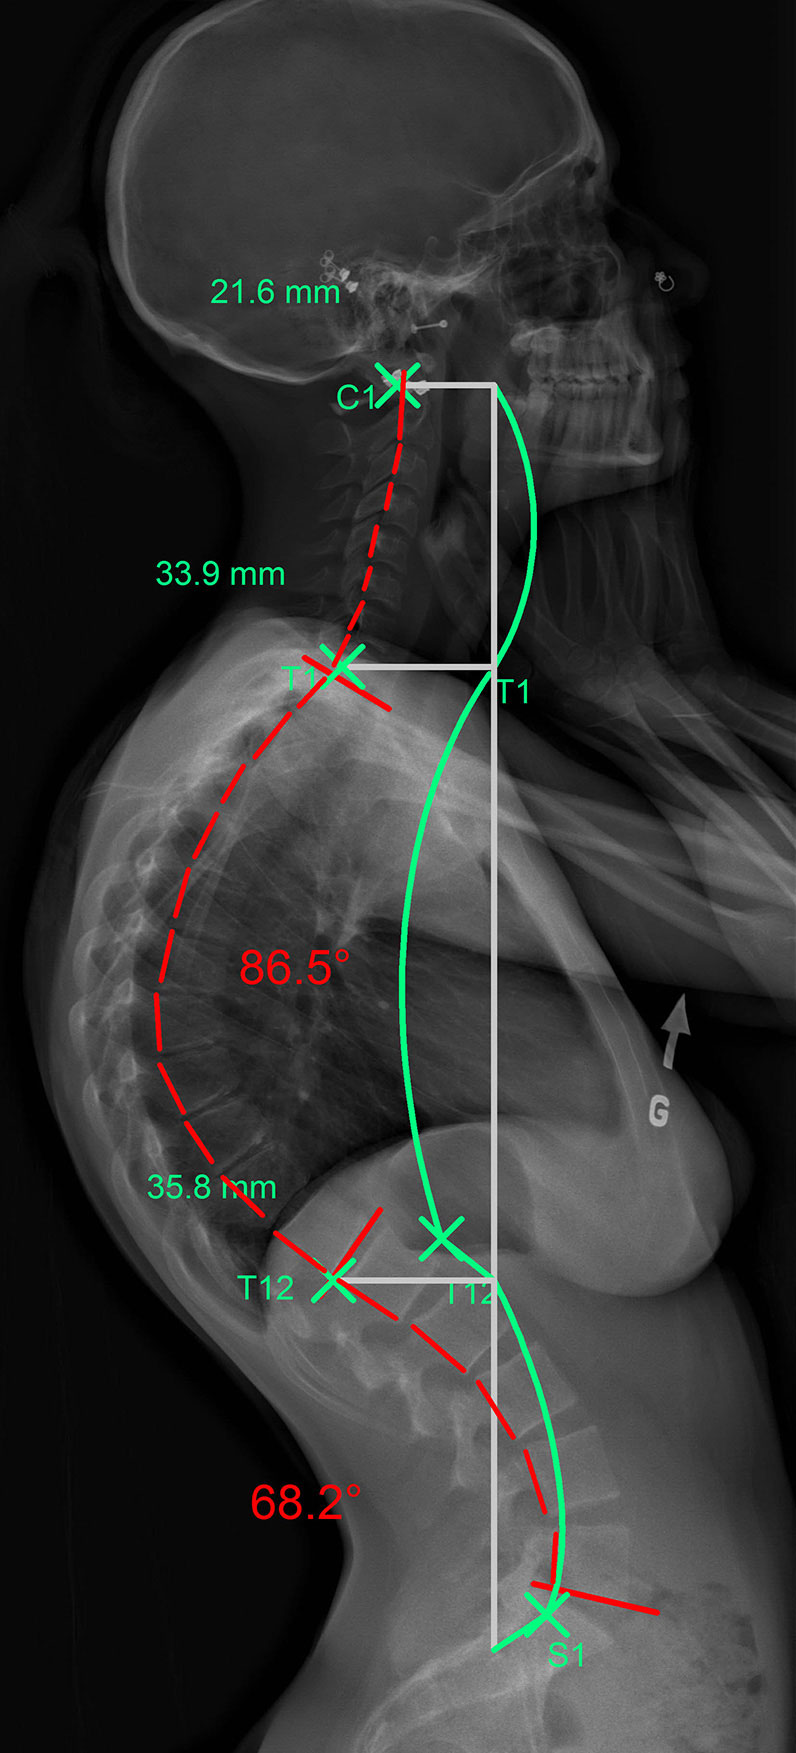

Hyperkyphosis can affect different portions of the thoracic spine as shown in these images (the green line represents an ideal spine, the red line represents the patient’s abnormal kyphotic curvature):

The green line represents the ideal spinal curvature and the red line that of the patient’s spine in profile view.